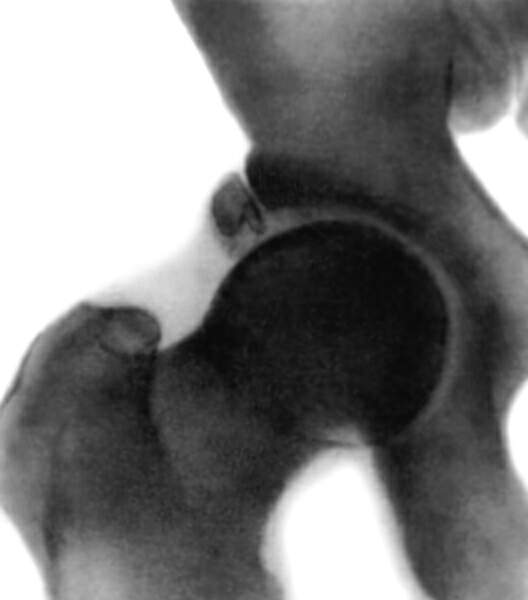

Оссификация тазобедренных суставов: что это и как проявляется?

Раздел: Сокровищница опыта